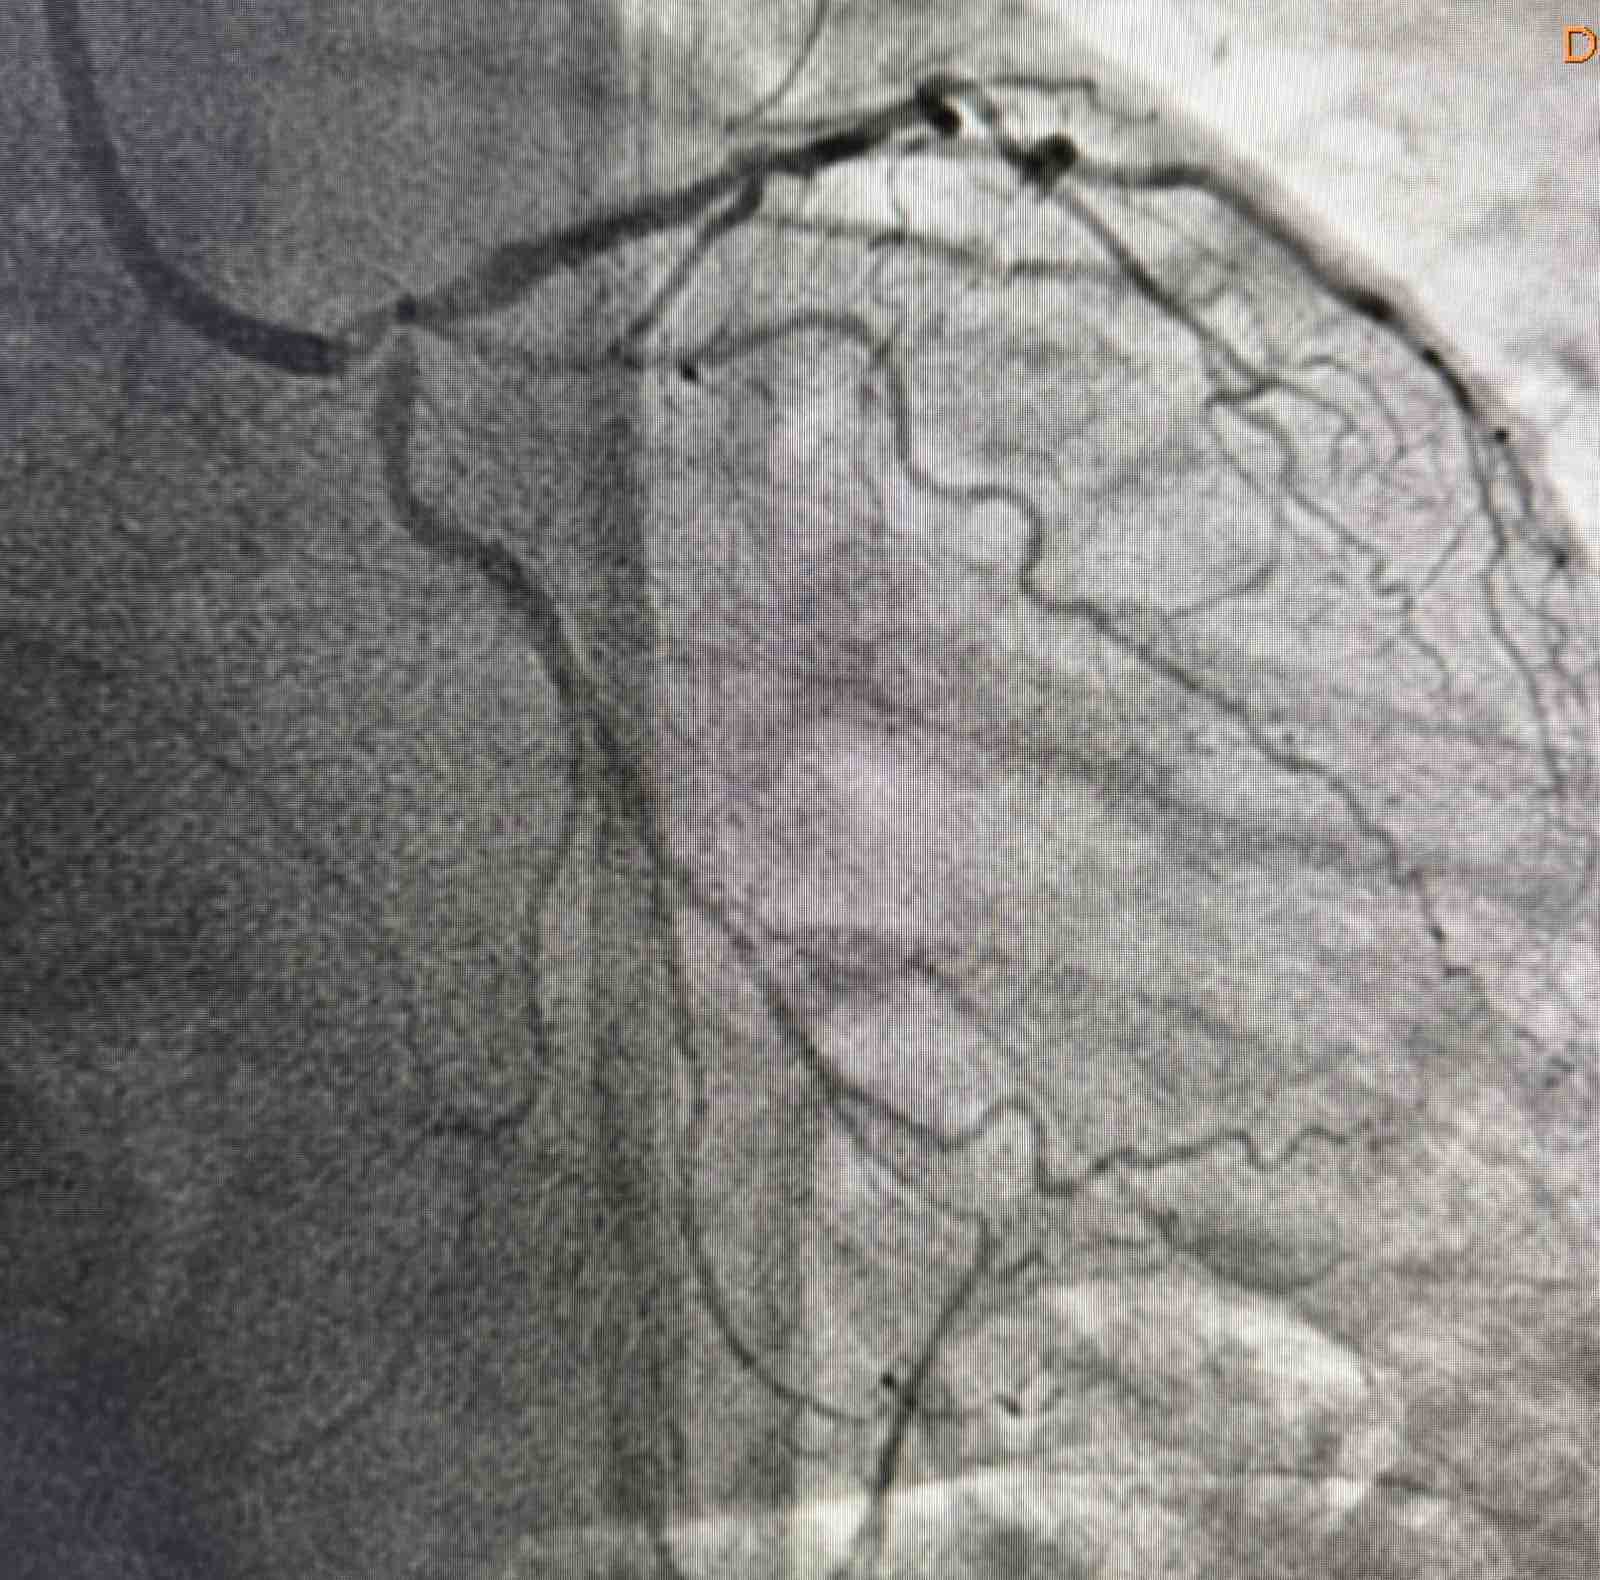

Tokom dva dana u angio sali izvedene su i izuzetno složene intervencije na koronarnim arterijama srca, uključujući perkutane intervencije na hronično - potpuno zapušenim krvnim sudovima srca i intervencije na tzv. glavnom stablu (left main) koja je glavna artrija srca i čije liječenje takođe spada u veoma rizične zahvate u interventnoj kardiologiji.

Još jedan slučaj koji izdvajamo kao posebno složen je bio kod pacijenta O.M (81), kod kojeg je dijagnostikovana teška trosudovna koronarna bolest.

„Pacijent je imao simptome angine pectoris. Nakon urađene koronarografije verifikovana je teška trosudovna koronarna bolest, gdje su bolesne bile desna koronarna arterija, dok je na lijevoj strani kritično mjesto bilo na glavnom stablu  odakle ide račvanje u dvije grane. Takvi pacijenti uglavnom završavaju na kardiohirurškom konzilijumu i na operaciji bajpasevima. Međutim, odluka konzilijuma u Banjaluci je bila da se, zbog godina života pacijenta,  radi perkutana intervencija na desnoj i lijevoj koronarnoj arteriji uključujući glavno stablo.Takve procedure zahtijevaju da se rade sa kontrolom imidžinga, savremene intravaskularne dijagnostike (IVUS), što smo mi i uradili. To dodatno povećava bezbijednost i preciznost zahvata. Procedura je trajala svega 45 minuta, a pacijent je već narednog dana otpušten kući“, izjavio je dr Janjičić.